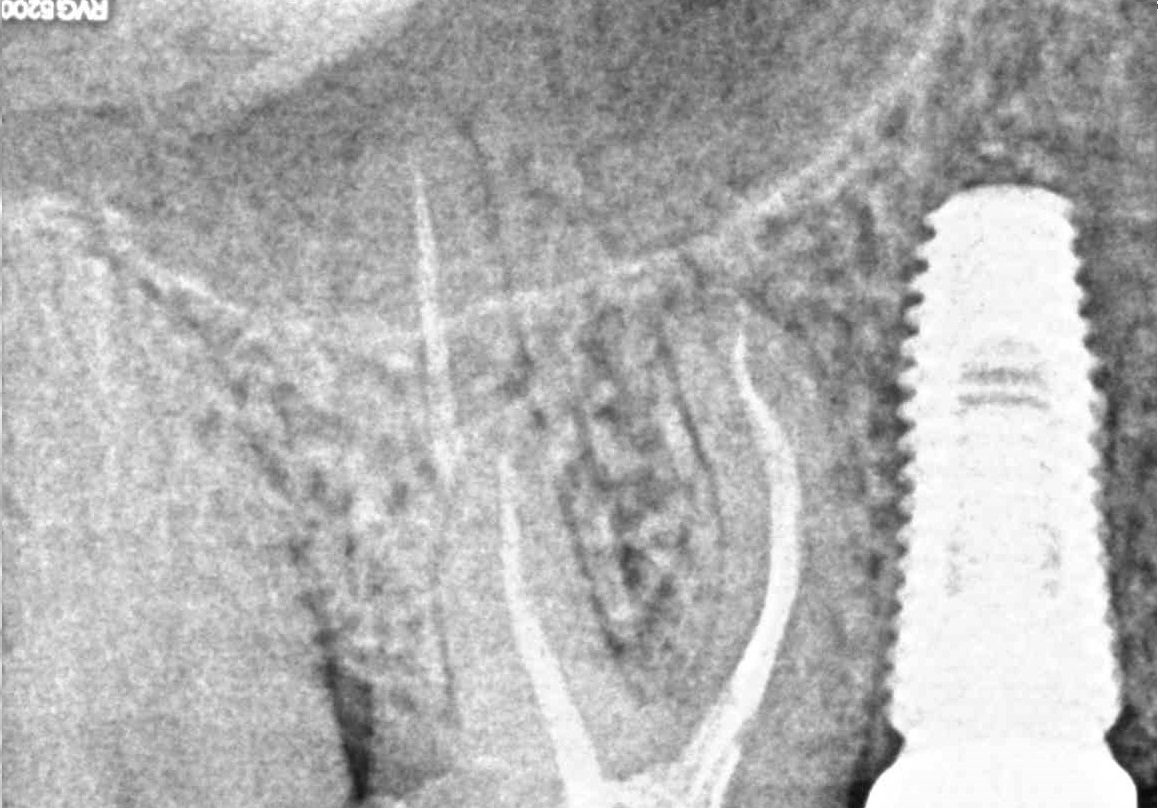

Примеры работ

- Лечение периодонтита

Проблема

Пациент обратился в клинику с постоянными ноющими самопроизвольными болями в зубе, усиливающиеся при накусывании, отечность тканей в области причинного зуба. После детального обследования были обнаружены значительные очаги воспаления на корнях зуба.Решение

Пациенту было проведено эндодонтическое лечение данного зуба. В результате лечения наблюдаем восстановление костной ткани, окружающей зуб.